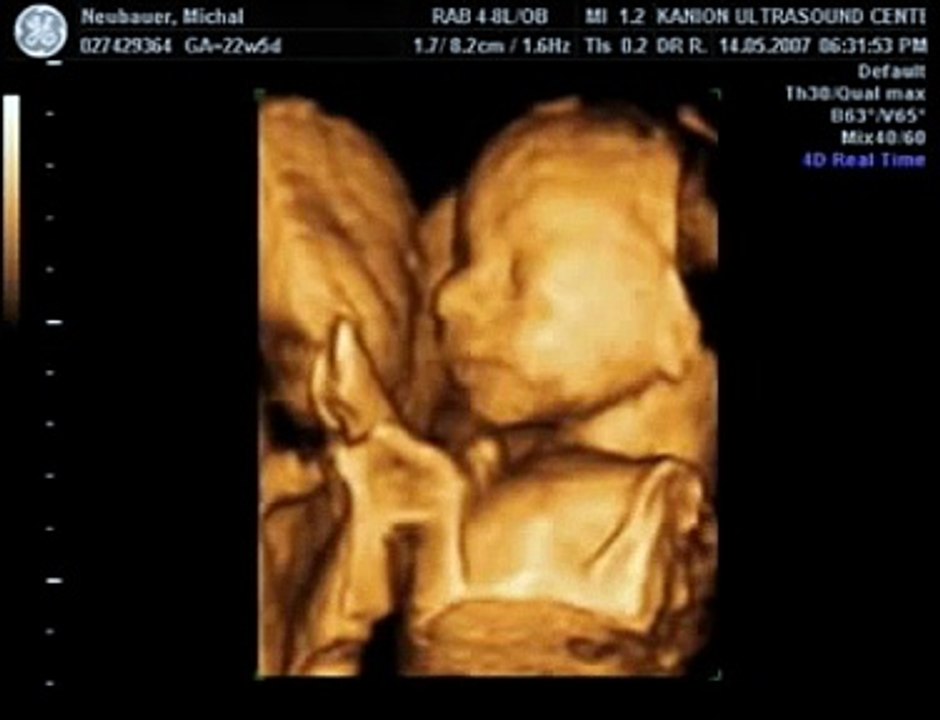

31 weeks 3d ultrasound video. Ecografia 4d 3d dr. Rafael ortega munoz ginecologo especialista en ecografias 4d ciudad real 52485 views. Robert hamilton demonstrates the hold. 3d ultrasound video at 31 weeks from goldenview ultrasound ny duration.

4d ultrasound 32 weeks pregnant face 4d rafael ortega munoz md ciudad real duration. We cant wait to meet him soon really soon. 3d ultrasound 30 weeks yawning baby a new conception 3d duration. 31 weeks 3d ultrasound.